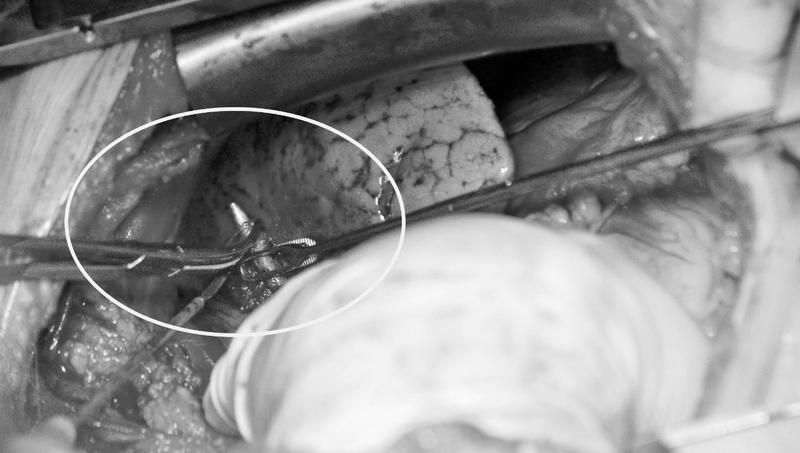

Коварство пятисантиметровой пули остановлено кардиохирургами госпиталя Вишневского